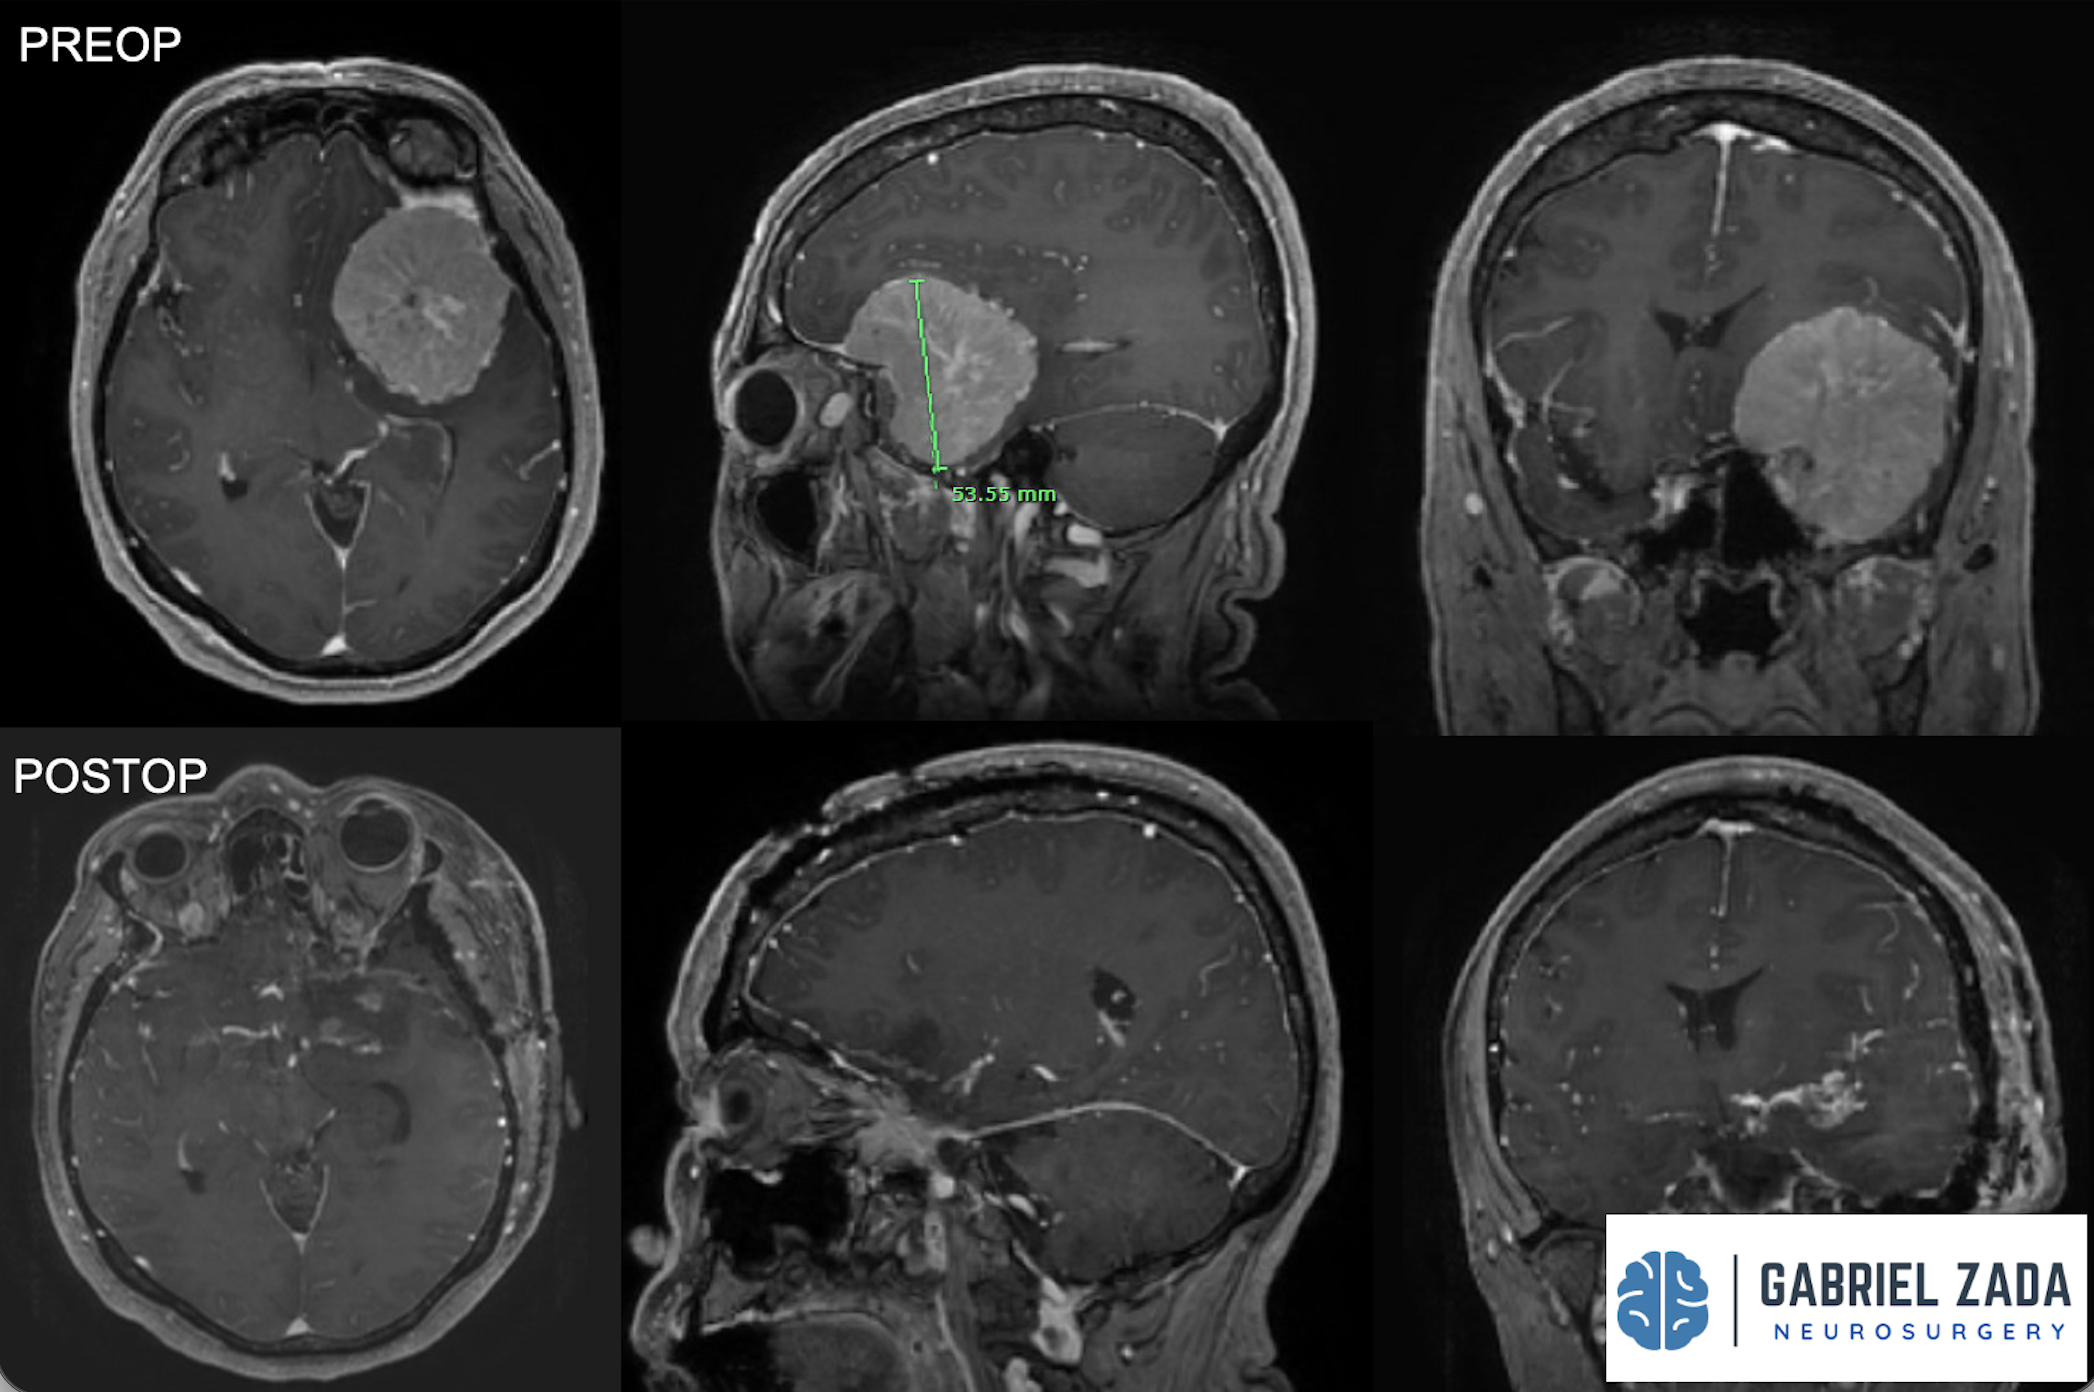

With extensive experience in advanced neurosurgical techniques, Dr. Zada provides personalized care for patients with meningiomas located in the brain and skull base. His approach emphasizes maximizing tumor removal while preserving neurological function, using modern imaging, microsurgical techniques, and minimally invasive approaches whenever possible.

Dr. Zada utilizes state-of-the-art neurosurgical techniques to safely remove meningiomas while protecting surrounding brain structures.

High-powered surgical microscopes allow precise tumor removal while minimizing damage to healthy tissue.

Advanced navigation systems help guide the surgeon with real-time imaging for enhanced precision.

• Follow-up MRI imaging to monitor results

* Representative cases shown for educational purposes. All images de-identified. Individual results vary.